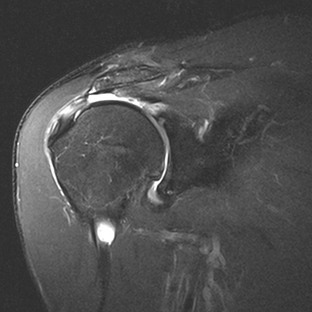

Although conventional MRI is established as the imaging modality of choice in the evaluation of shoulder impingement syndrome, MRA is accepted as the method of choice for the evaluation of glenohumeral instability.22,23 Many of the lesions associated with instability are subtle and may undergo partial healing. This situation, coupled with the fact that the normal anatomic structures of the shoulder lie in close proximity, can make the diagnosis of these lesions difficult even with high-quality conventional MRI.58-62 MRA, on the other hand, is performed by distending the joint with fluid (saline solution or dilute gadolinium), which more accurately depicts subtle labral tears, cartilage and ligamentous abnormalities, and partial-thickness tears of the undersurface of the rotator cuff. The standard injection technique for MRA of the shoulder is described in previous sections. About 12 to 14 mL of gadolinium diluted 1 : 200 with normal saline solution or 1% lidocaine is injected. Imaging protocols vary, but a standard set of imaging sequences typically includes T1-weighted images with frequency-selective fat saturation in the axial, oblique sagittal, and oblique coronal planes. The T1-weighted images have a high signal/noise ratio, resulting in the anatomic detail that is critical in detecting the subtle lesions associated with glenohumeral instability. A T2-weighted sequence performed in the oblique coronal plane is the most important sequence for depicting rotator cuff abnormalities. A T2-weighted sequence may also be helpful in detecting other pathologic processes, such as a paralabral cyst or bone marrow edema (Fig. 44-7, A and B). The ABER view may be added to the standard imaging protocol for any patient thought to have an anterior labral pathologic process.54

Anterior and lateral downward sloping of the anterior acromion can also narrow the supraspinatus outlet and potentially result in impingement.80,81 Anterior downward sloping (see Fig. 44-11, B) is demonstrated on oblique sagittal MRI; lateral downward sloping (see Fig. 44-11, C) is best seen on the oblique coronal images. An enthesophyte (Fig. 44-12) extending off the anteroinferior aspect of the acromion can also be clearly demonstrated on MRI. It typically appears as a marrow-containing osseous excrescence, which should have MRI signal characteristics similar to those of the adjacent acromion marrow (bright on T1-weighted images). Potential pitfalls include the attachment of the coracoacromial ligament and the deltoid tendon insertion (see Fig. 44-11, A and C) on the anterior acromion. These structures may mimic an osseous excrescence, but they can be differentiated from enthesophytes because they lack marrow signal and appear dark on all pulse sequences. The acromion should also be evaluated for os acromiale (Fig. 44-13), which is an accessory ossification center along the outer edge of the anterior acromion. It is normally fused by 25 years of age. An association exists between persistent os acromiale and impingement of the rotator cuff.82-86 The deltoid muscle attaches to the inferior aspect of the accessory ossicle, and contraction of the deltoid results in a downward motion of the unstable segment, potentially leading to impingement of the underlying rotator cuff. Os acromiale is demonstrated best on axial images (see Fig. 44-7, A), but it can also be seen on oblique sagittal or oblique coronal images (see Fig. 44-7, B),85 on which it should not be confused with the adjacent AC joint. MRI signs of instability of the os acromiale include fluid signal within the synchondrosis or sclerosis, cystic change, or marrow edema on either side of the synchondrosis (Box 44-2).